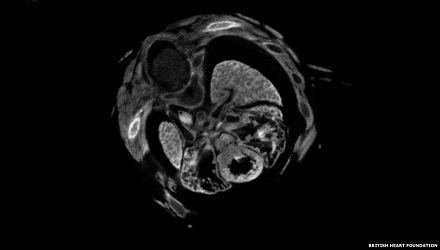

الصورة الأولى: نشر العلماء في بريطانيا صورا ولقطات فيديو من بحوثهم. وتظهر الصور لقطات مدهشة للقلب وأوعيته الدموية. الصورة الفائزة "قلب مفطور" للدكتورة جيليان غاري، وميغان سويم، وهاريس موريسون، من جامعة إدنبره تبين تركيب القلب من الداخل.

الصورة السابعة: كما نال فيديو "السفر عبر قلب جنين، للدكتور دانيال ديلغ من جامعة لندن تعليقات كثيرة، وهو يظهر نمو القلب والرئتين في مقطع واحد بالنظر من أعلى، ثم يتبع ذلك قلب مصاب بفتحة في الجدار الفاصل بين جزئيه الأعلى والأسفل. والفهم الأفضل لمثل تلك الحالة قد يؤدي إلى اكتشاف سبل لمنعها.